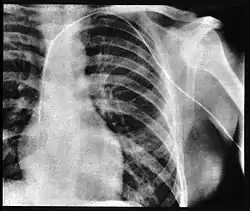

Er nutzte den Zugang über die linke Vena cephalica, eine große Blutader an der Außenseite des Oberarms. Er schob den Katheter 65 Zentimeter weit bis in die rechte Herzkammer und führte ihn durch die Oberarmvene in die Vena subclavia und von dort durch die Vena brachiocephalica und die obere Hohlvene (Vena cava superior) in den rechten Herzvorhof.[22] Dies dokumentierte er mit einer Röntgenaufnahme,[22] für die er (nach der Schilderung in der Autobiografie) mit dem eingeführten Katheter in den Röntgenkeller der Klinik ging und mit Hilfe einer Röntgenschwester ein Bild von dem Schlauch in der rechten Herzkammer machte.[4][12][21]

Am 5. November publizierte die Klinische Wochenschrift seine Arbeit Über die Sondierung des rechten Herzens.[22] Sie fand aber – ähnlich wie im April 1931 sein Vortrag auf der Tagung der Deutschen Gesellschaft für Chirurgie – in der Fachwelt kaum Resonanz.[23] Forßmann stellte die Katheterisierung vor allem als Alternative der seinerzeit häufig bei Akutbehandlungen angewandten und aufgrund möglicher Verletzung des Herzens und der umgebenden Gefäße sehr riskanten intrakardialen Injektion dar, um eine schnelle örtliche Arzneibehandlung zu gewährleisten.[22] Neben seinem Selbstversuch beschrieb er in diesem Artikel auch die erfolgreiche klinische Anwendung bei der Behandlung einer Patientin mit eitriger Bauchfellentzündung, bei der er den Rechtsherzkatheter zur Medikation einsetzte. Dabei blieb der Katheter 6,5 Stunden im Herzen der Patientin, die jedoch nach kurzer Besserung an ihrer Erkrankung verstarb. Bei der Obduktion fand er den Katheter tatsächlich im Herzen und in der unteren Hohlvene vor; er konnte keine durch den Katheter verursachten Verletzungen in den Venen feststellen.[22] Laut seiner Autobiographie erfolgte die Behandlung der im Sterben liegenden Patientin, deren Bauchfellentzündung von einer Fehlgeburt herrührte, erst nachdem er den Katheter an sich selbst getestet hatte. Er nutzte diesen Versuch nachträglich als Bestätigung seines Selbstversuchs.[24][25]